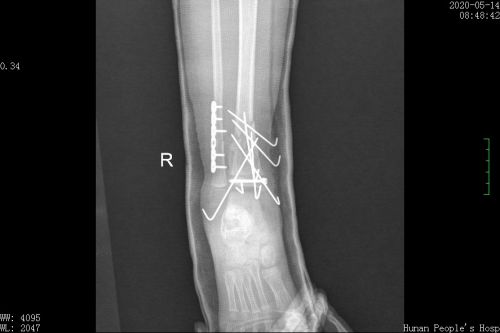

右侧腓骨骨折切开复位内固定+右侧胫骨骨骺骨折复位克氏针及螺钉固定术后。